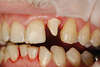

1- Les implants dans le cas d'un accident :

Cette incisive a été fracturée suite à un accident                           Il a été possible de la remplacer par un implant

Cet implant supporte un pilier personnalisé en Zircon qui permet de soutenir la couronne

Résultat après 6 mois